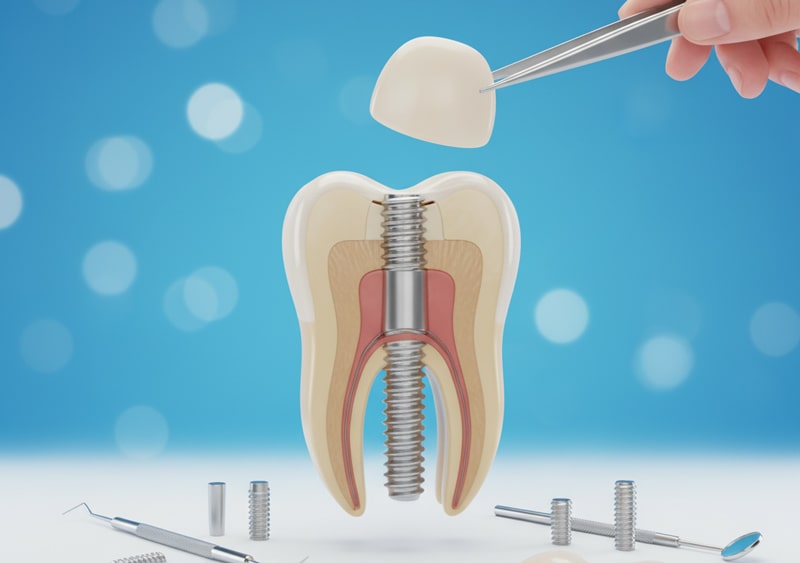

ایمپلنت دندان یکی از بهترین روش ها جهت جایگزینی دندان های از دست رفته می باشد؛ ایمپلنت در واقع نوعی پایه تیتانیومی است که در

یکی از بهترین روش های جایگزینی دندان، ایمپلنت است، ایمپلنت دندان به دلیل ماندگاری بالایی که دارد از محبوبیت بالایی برخوردار است. در این روش یک پیچ از جنس تیتانیوم، در استخوان فک به عنوان ریشه کاشته می شود و روی آن یک روکش قرار می گیرد. ایمپلنت یا کاشت دندان معمولا از بقیه روش ها قیمت بیشتری دارد. ایمپلنت دندان مستعد شرایط فک و لثه مناسب نیز است.